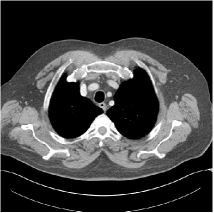

Refer to caption WavResNet [11]Refer to caption WavResNet [11]Refer to caption WavResNet [11]Refer to caption Momentum-Net (SimpleCNN)Refer to caption Momentum-Net (SimpleCNN)Refer to caption Momentum-Net (SimpleCNN)Refer to caption Momentum-Net (SimpleCNN-RSN)Refer to caption Momentum-Net (SimpleCNN-RSN)Refer to caption Momentum-Net (SimpleCNN-RSN)Refer to caption Momentum-Net (Dn-RSN)Refer to caption Momentum-Net (Dn-RSN)Refer to caption Momentum-Net (Dn-RSN)Refer to caption ReferenceRefer to caption ReferenceRefer to caption Reference

Fig. 3: Three examples (from top to bottom) of the reconstructed testing images using Momentum-Net with SimpleCNN (the second column), with SimpleCNN-RSN (the third column), and with Dn-RSN (the fourth column). The compared WavResNet denoised images are shown in the first column, and the reference images are in the fifth column. See their FBP images in Fig. 4.

Fig. 2 shows that the proposed Momentum-Net with SimpleCNN decreases RMSE dramatically in the first 30 layers, and tends to converge in 50 layers. The Momentum-Net reduces the mean RMSE value by 4.5 HU and gives smaller standard deviations in RMSE, compared to WavResNet, as reported in Table 1. This implies that the proposed Momentum-Net with SimpleCNN can improve both the accuracy and stability of low-dose CT image reconstruction than a state-of-the-art image denoising deep NN, WavResNet. The proposed Momentum-Net with SimpleCNN better removes noise and streak artifacts than WavResNet. It also provides clearer reconstructions of some details; see, in Fig. 3, the boundaries shown in the zoomed region at the top-right corner in the first example, the arrow pointed structures in zoomed areas of the second example, and the arrow pointed tissues in the left zoomed region in the third example.

3.3 Momentum-Nets involving RSN-based training